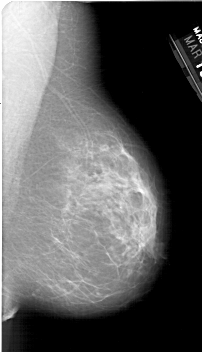

A_1387_1.RIGHT_CC